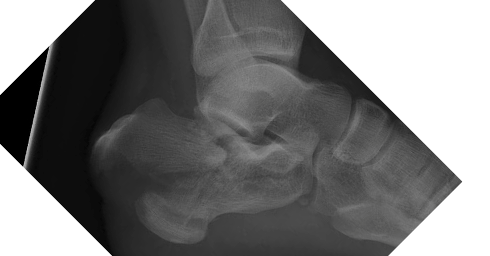

A calcaneus fracture is a break of the heel bone, which forms the foundation of the hindfoot and plays a critical role in weight bearing, balance, and walking. These fractures are often the result of high-energy trauma and can be associated with significant swelling, deformity, and long-term functional impairment.

The calcaneus is the largest bone in the foot and transmits forces from the ankle to the ground during standing and walking. When fractured, especially in high-energy injuries, the bone may collapse or fragment, disrupting the subtalar joint, which is essential for side-to-side motion of the foot.

Calcaneus fractures are broadly categorized as intra-articular (involving the joint surface) or extra-articular. Intra-articular fractures are more complex and carry a higher risk of long-term complications such as stiffness, deformity, and post-traumatic arthritis. Because of the surrounding soft-tissue envelope, these injuries require careful evaluation and treatment planning.

Imaging is essential for accurate diagnosis. X-rays are used to identify fracture patterns and alignment, while CT scans are frequently obtained to evaluate joint involvement, degree of comminution, and to assist with surgical planning.